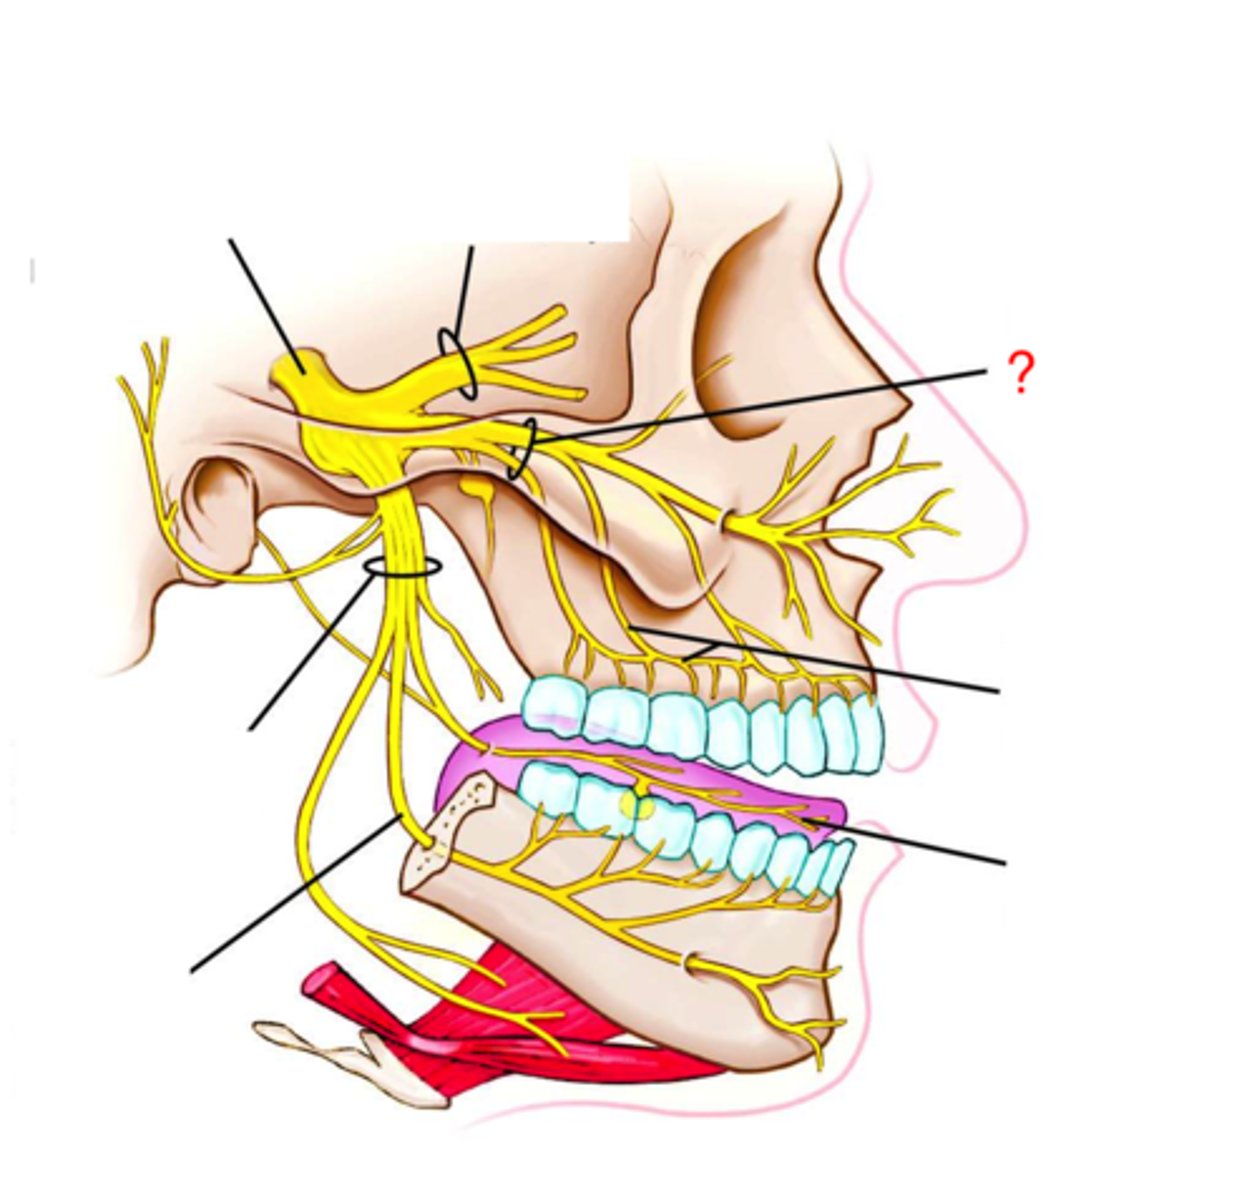

trigeminal nerve

inferior alveolar nerve

infraorbital nerve

maxillary nerve (V2)

Buccal nerve